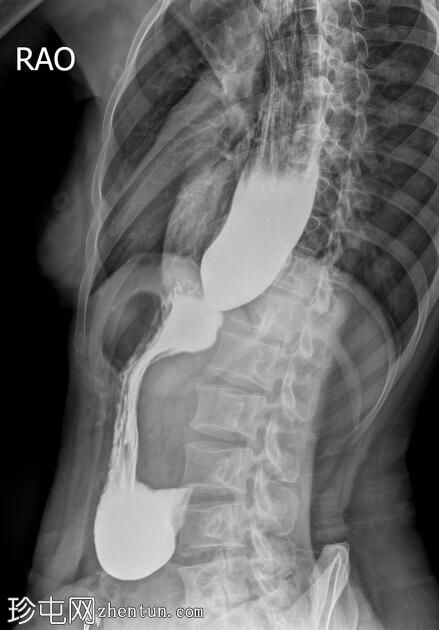

透视检查

斜位

食管扩张,远端平滑狭窄并呈锥形(鸟嘴状),符合贲门失弛症的特征性表现

食管黏膜形态正常,无异常或溃疡

未见食管裂孔疝

钡餐检查显示食管扩张,远端狭窄并呈锥形,形成符合贲门失弛症特征的鸟嘴状外观。